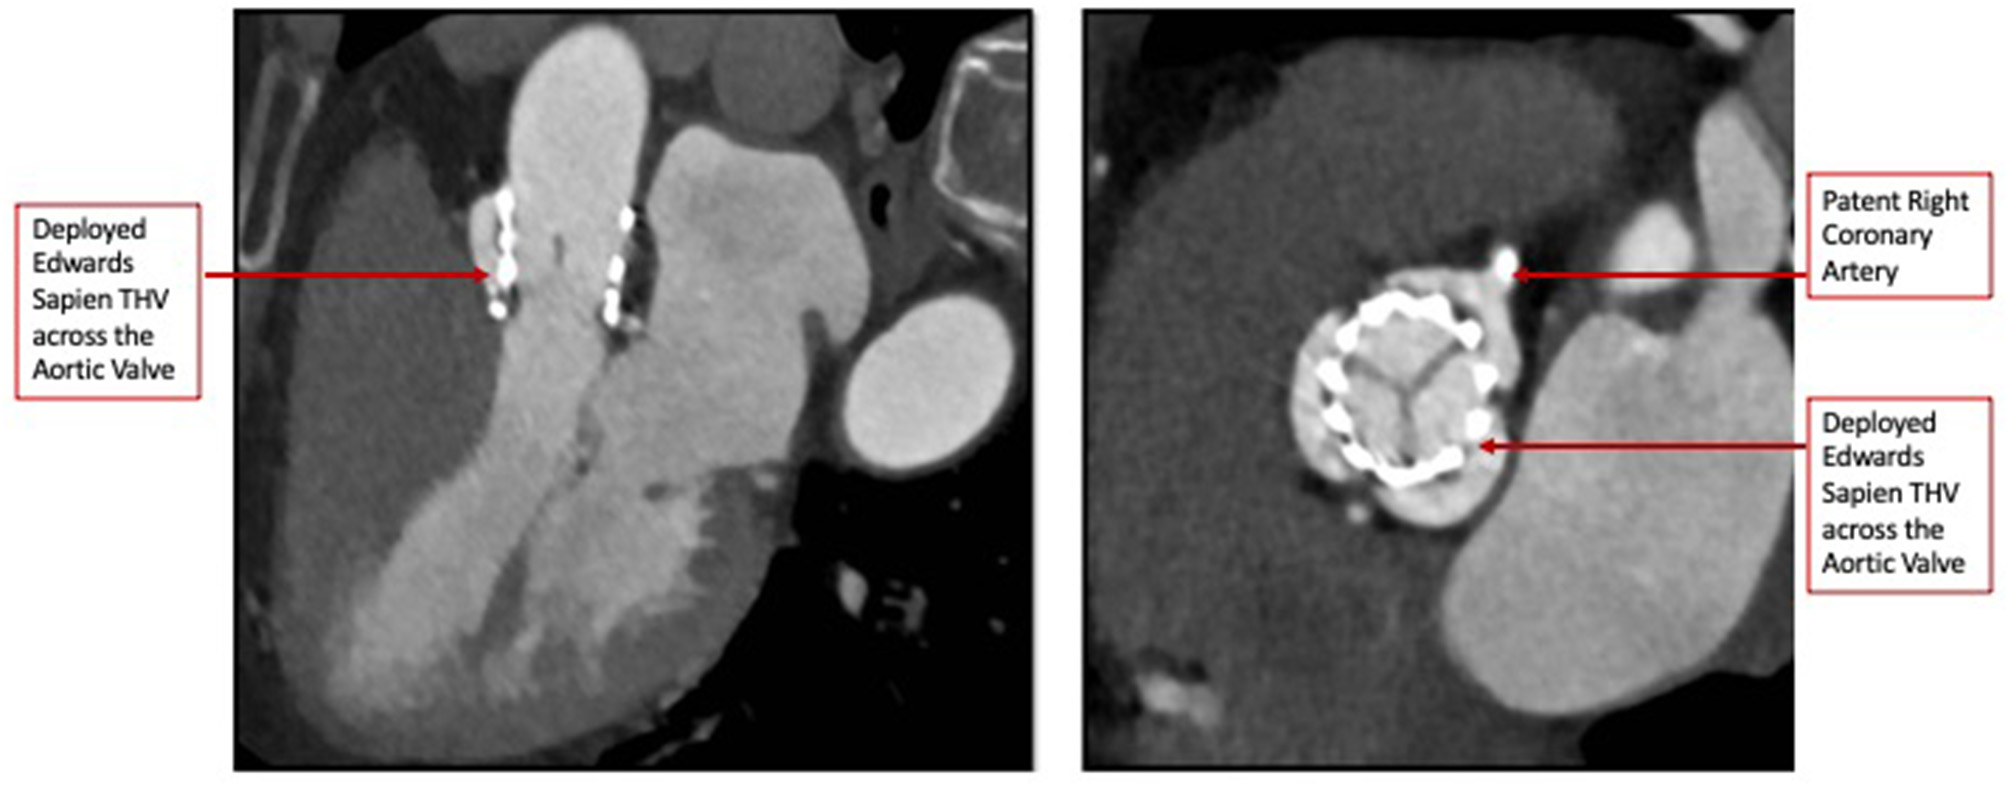

The heart team-meeting consensus was to proceed with TAVR using an Edwards SAPIEN valve with high implant. Alternate access should be obtained to rescue the anomalous LCX. The patient underwent the procedure successfully as follows: Through the left common femoral vein sheath, a temporary pacing wire was inserted. Through the left arterial sheath, a pigtail was advanced. Through the right arterial sheath, an Edwards SAPIEN delivery sheath was advanced over a Sapphire wire that had been placed in the LV through the standard method. The valve was predilated using rapid pacing, and an angiogram through the pigtail catheter demonstrated a patent RCA, LCX, and LM artery ostial with some compression of the LCX midsegment. As such, the decision was to proceed as planned with a high implant of the Edwards SAPIEN valve (Figure 2). The implant was performed with rapid ventricular pacing. Angiography using a power injector confirmed appropriate expansion of the valve and no paravalvular regurgitation. Selective angiography of the LCX with a 6-French AL 0.75 guiding catheter confirmed widely patent coronary arteries (Figure 3). The echocardiogram further confirmed the angiographic findings. Post procedure, the gradient by echocardiography was 7 mmHg, and the EF had improved to 44.5% (Supplementary Figure 2). The improvement in EF could be due to inter-observer variability although it is uncommon to be this wide of a range. It may indicate timely replacement with improvement in the left ventricular systolic and diastolic functions. Imaging including cardiac MRI could identify fibrosis that may suggest poor recovery. This was not performed in this patient. The postoperative course was uneventful, and she was discharged on day 3 in stable condition without a need for a pacemaker on dual antiplatelet therapy (aspirin 81 mg and clopidogrel 75 mg daily). She was evaluated after 1 month at an outpatient clinic, where she was completely asymptomatic. A repeat CCT demonstrated thin leaflets with normal mobility and a widely patent LCX (Figure 4 and Supplementary Figure 3).

Figure 4

Post-TAVR Cardiac Computed Tomography images (Short and Long-axis) demonstrating thin mobile leaflets with no hypoattenuation.

It is important to recognize that the role of CCT was not restricted to the pre-procedure workup, but in the follow-up as well. We were able to non-invasively evaluate the valve position, leaflet thickness, and mobility and reassess the LCX patency in the follow-up CCT (10).